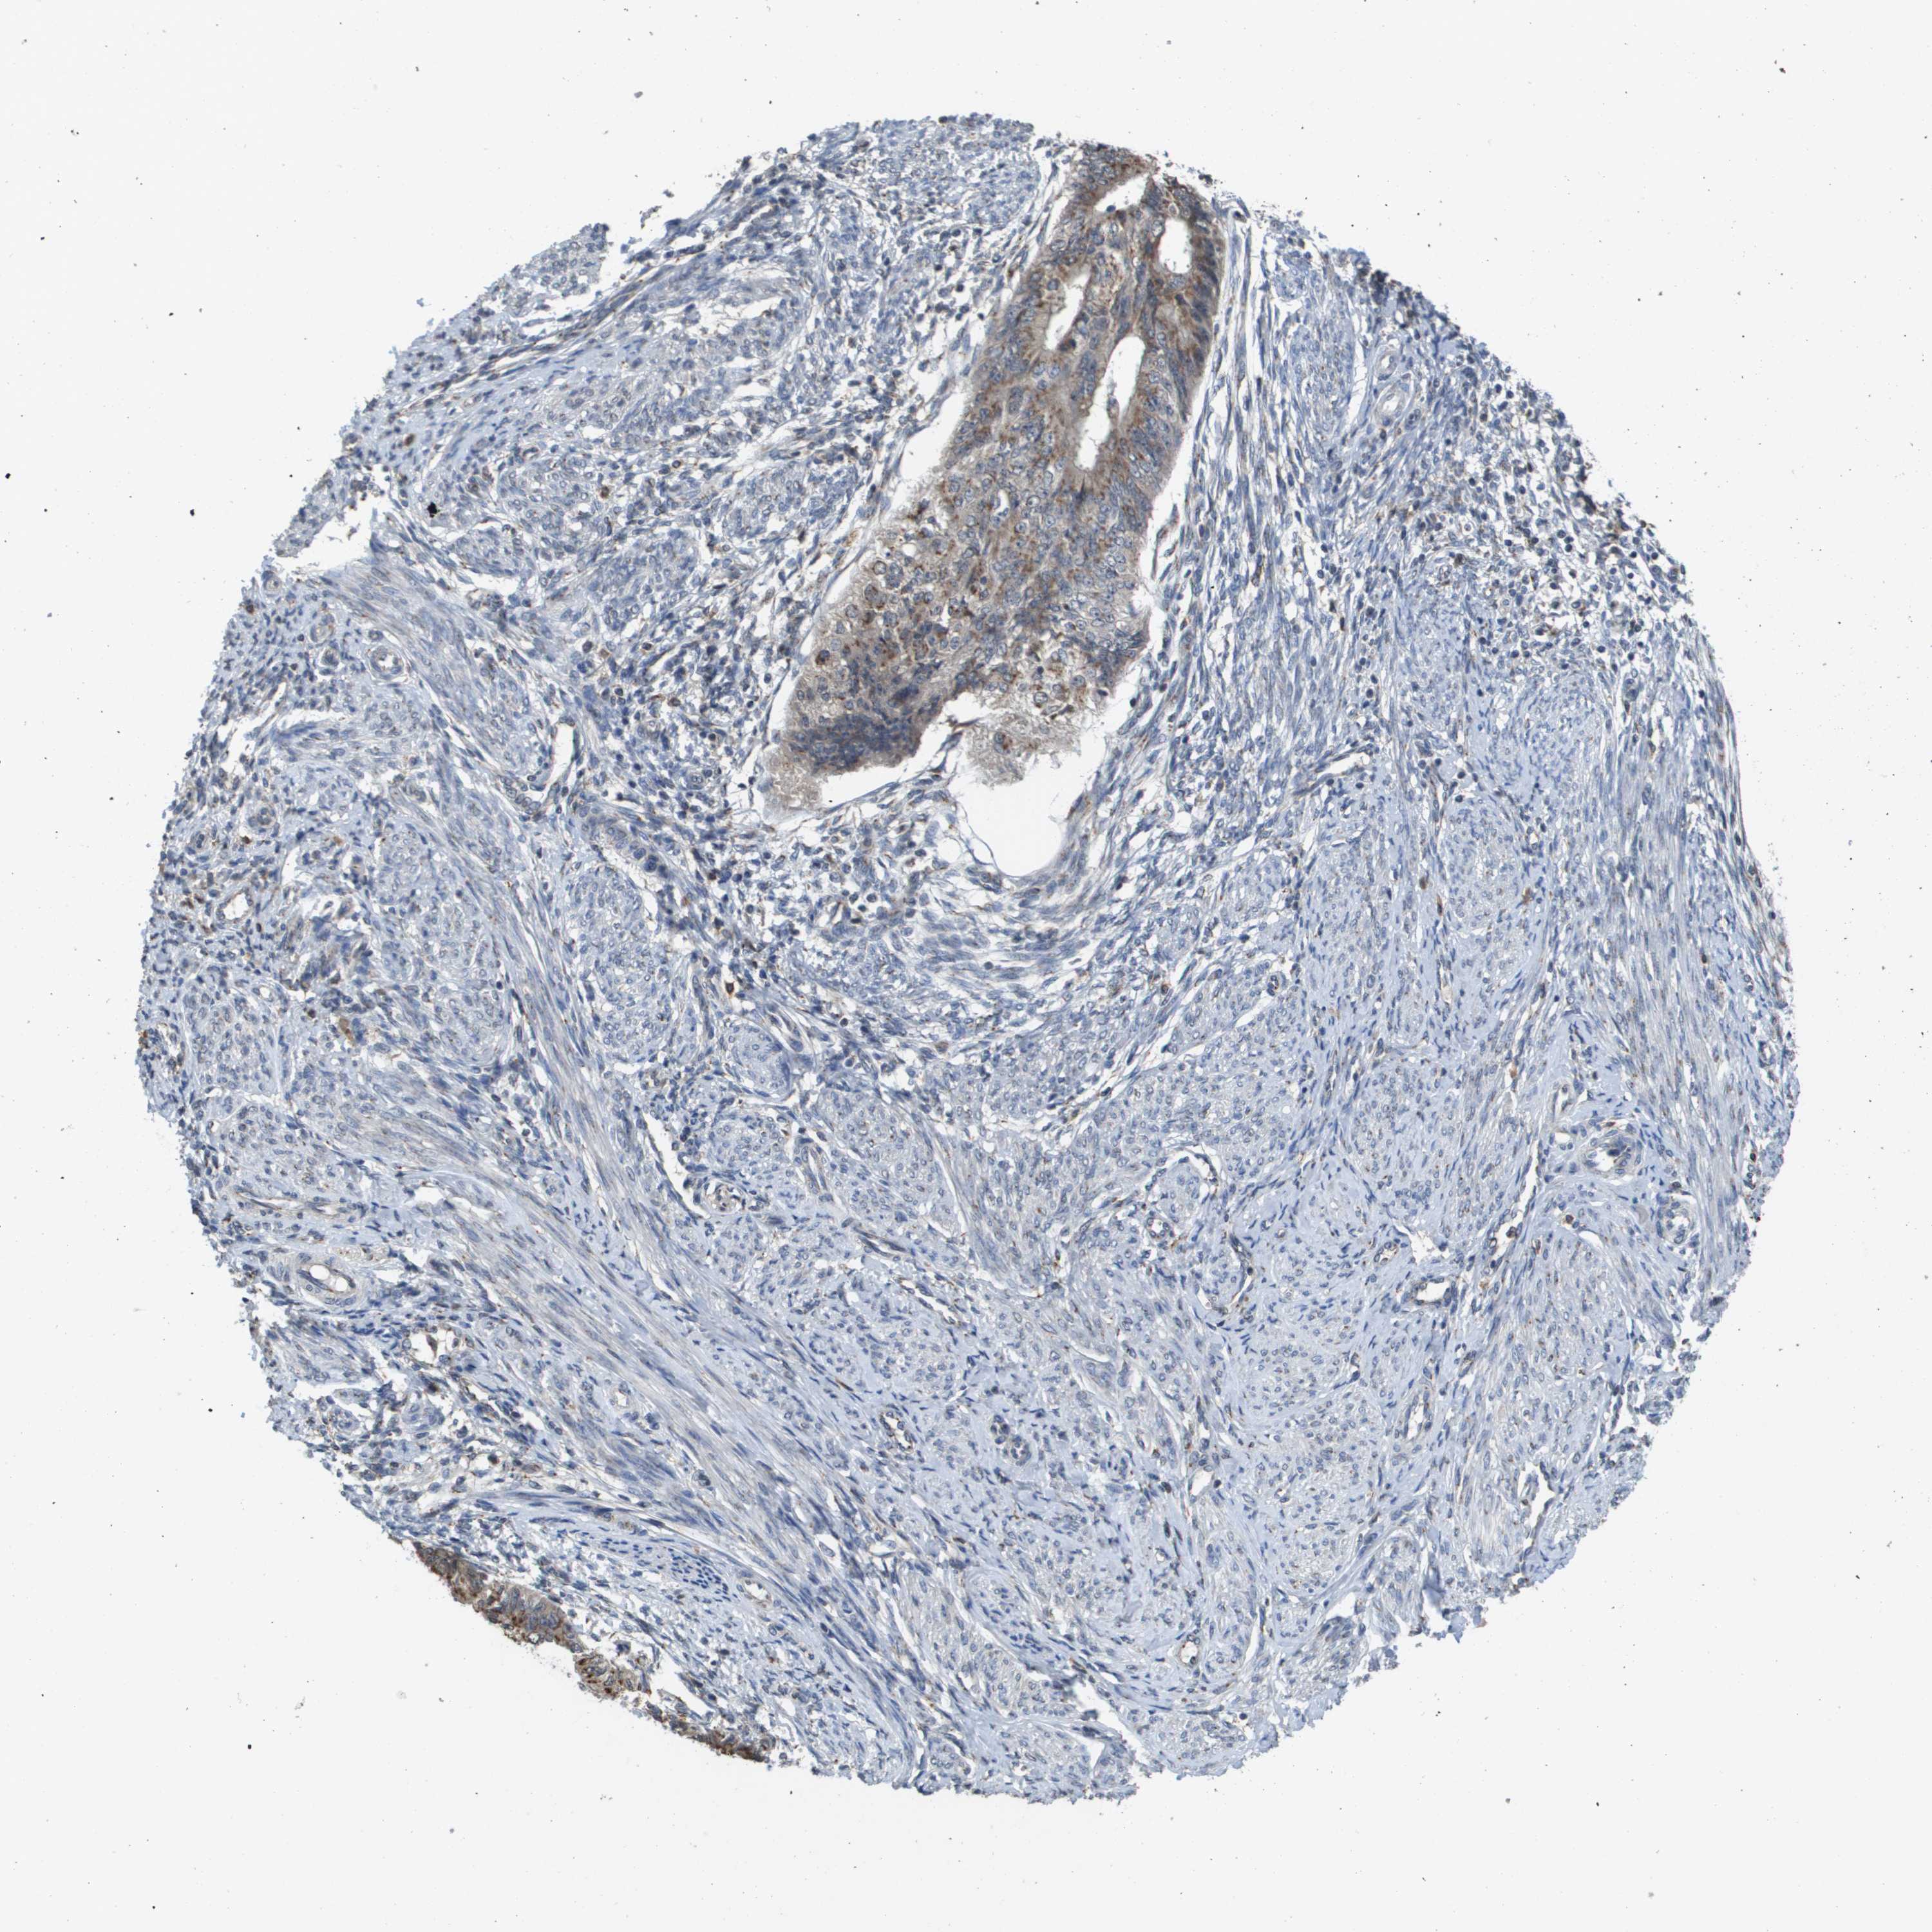

ENDOMETRIAL CANCER - Protein expressioni

A mouse-over function shows sample information and annotation data. Click on an image to view it in a full screen mode. Samples can be filtered based on level of antibody staining by selecting one or several of the following categories: high, medium, low and not detected. The assay and annotation is described here.

Note that samples used for immunohistochemistry by the Human Protein Atlas do not correspond to samples in the TCGA dataset.

Antibody stainingi

Antibody staining in the annotated cell types in the current human tissue is reported as not detected, low, medium, or high, based on conventional immunohistochemistry profiling in selected tissues. This score is based on the combination of the staining intensity and fraction of stained cells.

Each image is clickable and will lead to virtual microscopy that enables deeper exploration of all samples and also displays staining intensity scores, fraction scores and subcellular localization as well as patient and tissue information for each sample.

Antibody HPA006277

Antibody HPA006507

Antibody CAB017027

Staining

High

Medium

Low

Not detected

Intensity

Strong

Moderate

Weak

Negative

Quantity

>75%

75%-25%

<25%

None

Location

Nuclear

Cytoplasmic/membranous

Cytoplasmic/membranous,nuclear

Adenocarcinoma, NOS